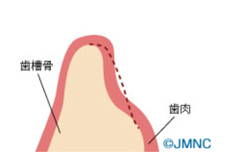

(図説)むし歯や歯周病などが原因で歯を抜歯すると、生体の反応として、歯を支えていた歯槽骨の一部が吸収してしまい写真のように骨幅・骨量が少なくなってしまいます。点線の部分は本来あるべき歯槽骨の厚みになりますが、歯槽骨が吸収してしまうと、インプラントを埋め込む際に必要な骨幅・骨量が足りなくなってしまいます。